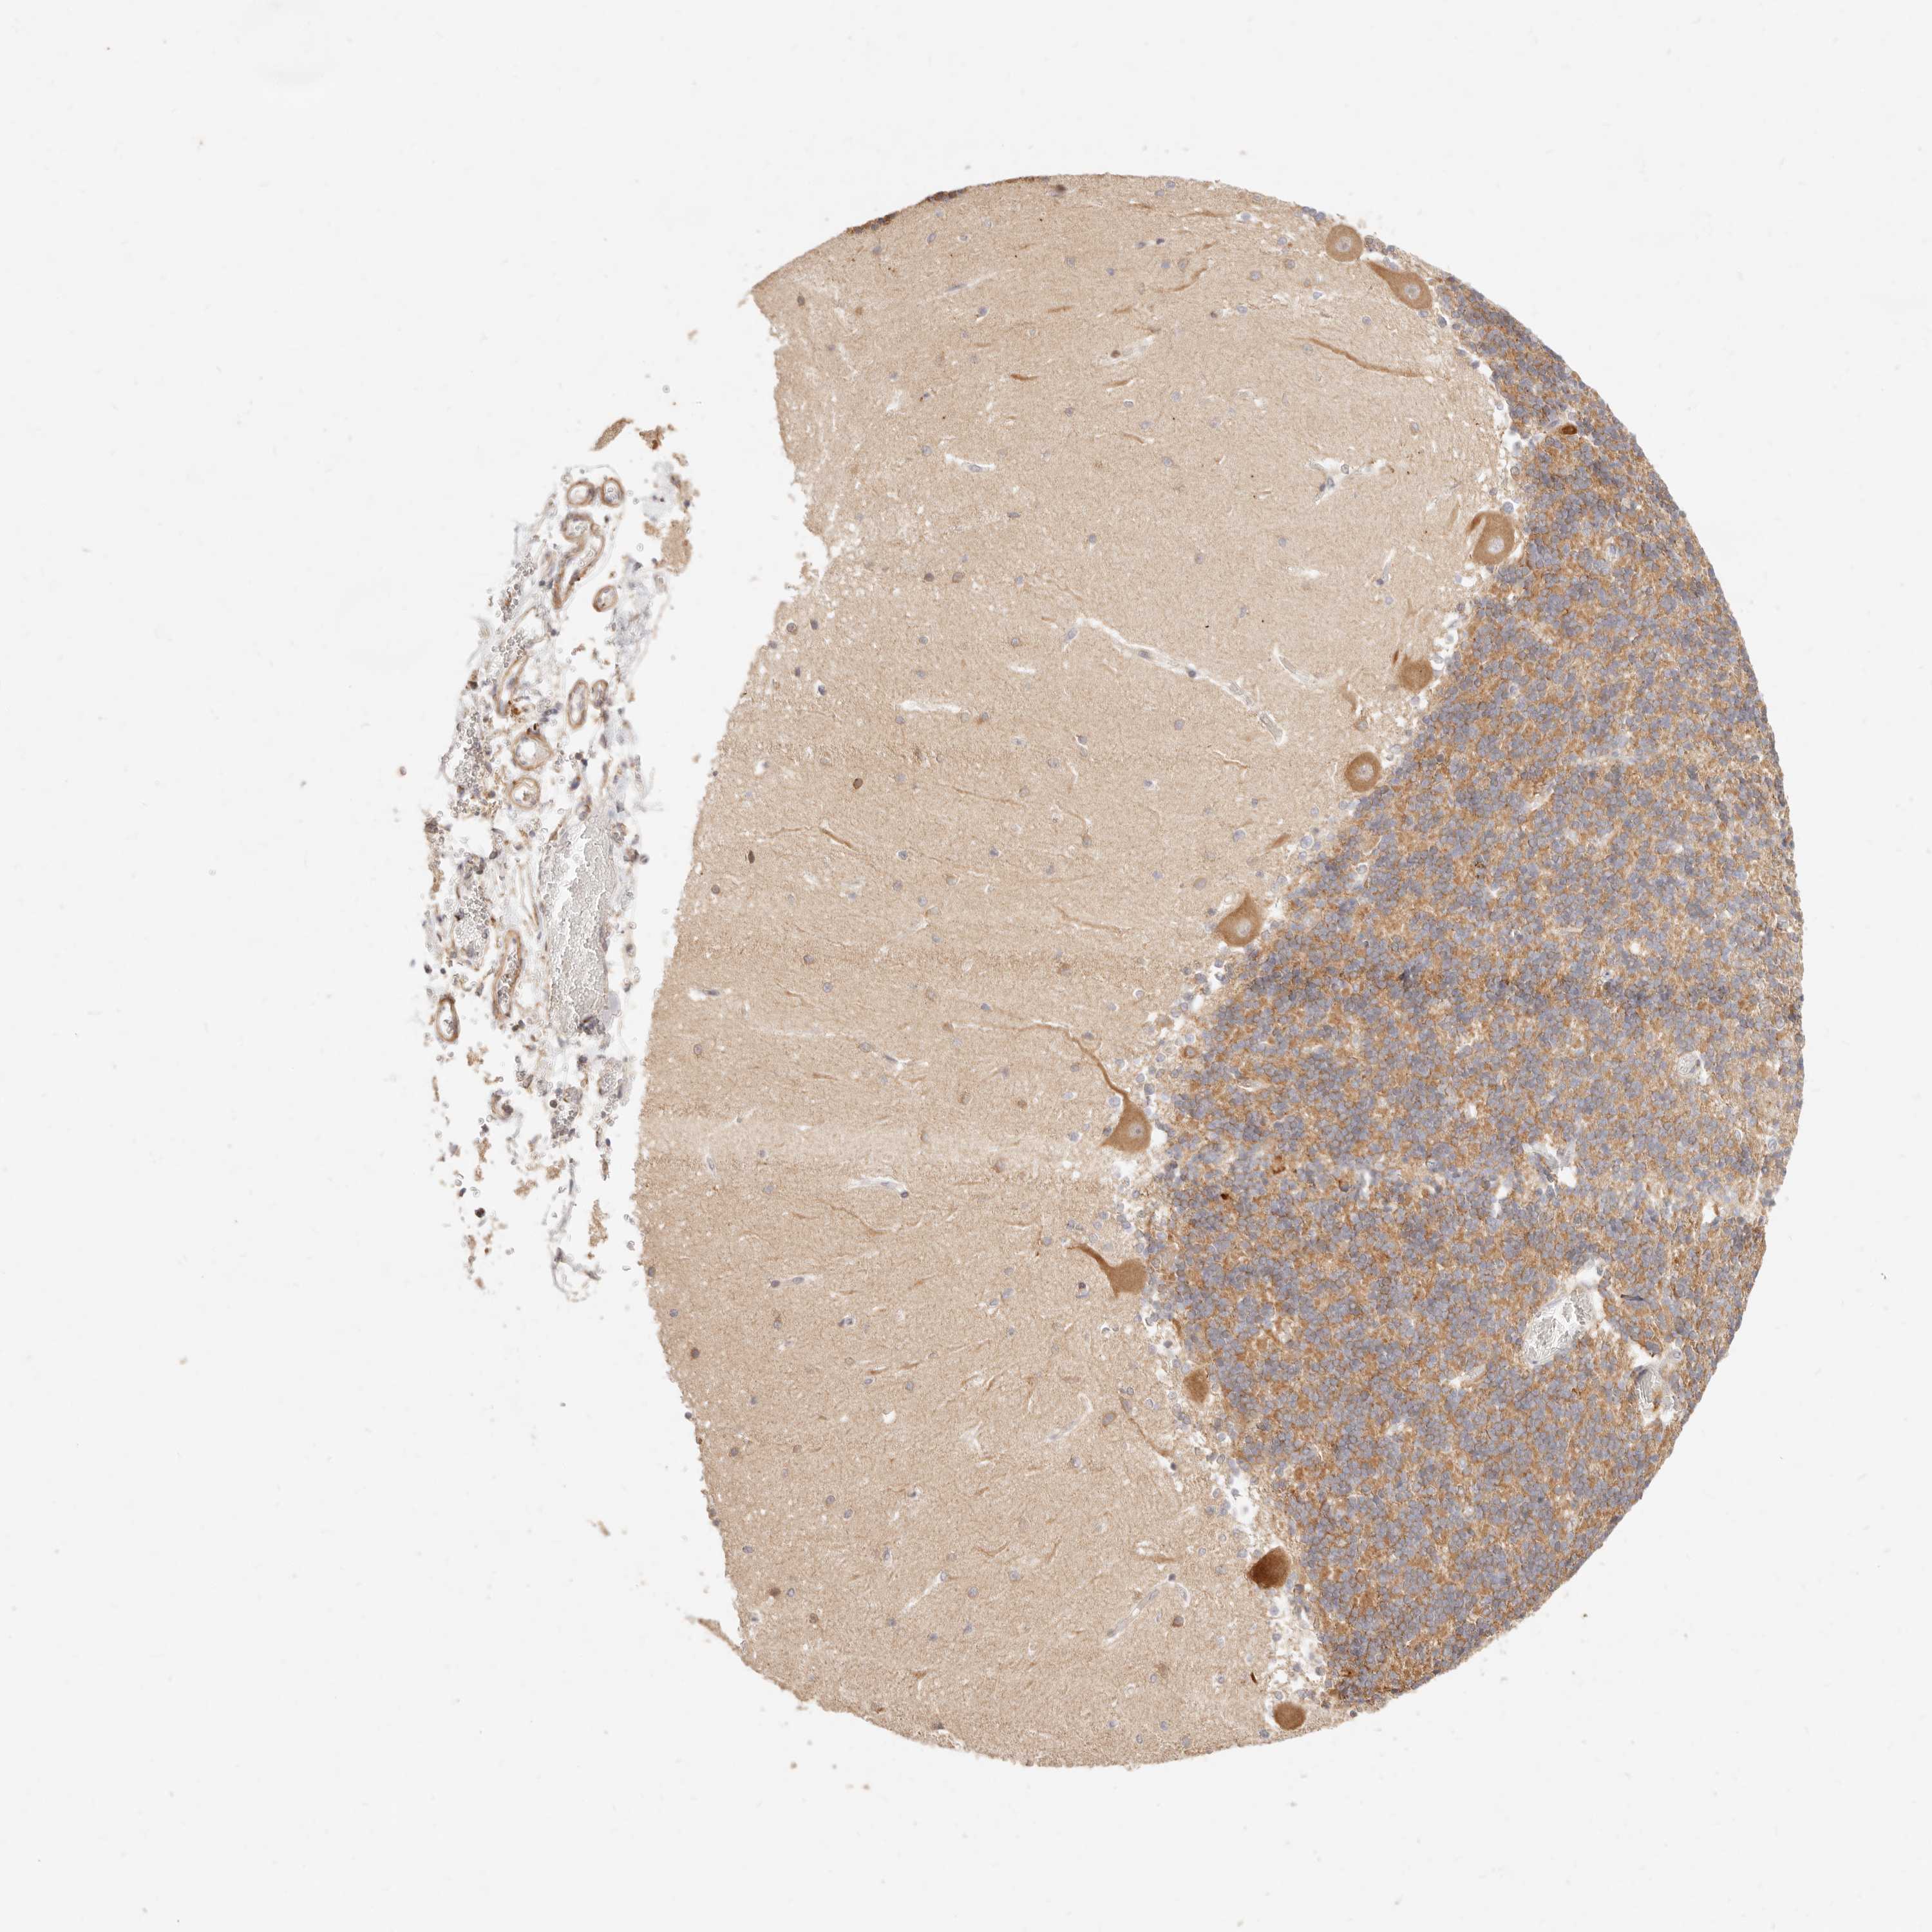

CEREBELLUM - Antibody stainingi

Antibody staining in the annotated cell types in the current human tissue is reported as not detected, low, medium, or high, based on conventional immunohistochemistry profiling in selected tissues. This score is based on the combination of the staining intensity and fraction of stained cells.

Each image is clickable and will lead to virtual microscopy that enables deeper exploration of all samples and also displays staining intensity scores, fraction scores and subcellular localization as well as patient and tissue information for each sample.

Antibody HPA026614

Purkinje cells Medium

Cells in granular layer Medium

Cells in molecular layer Low